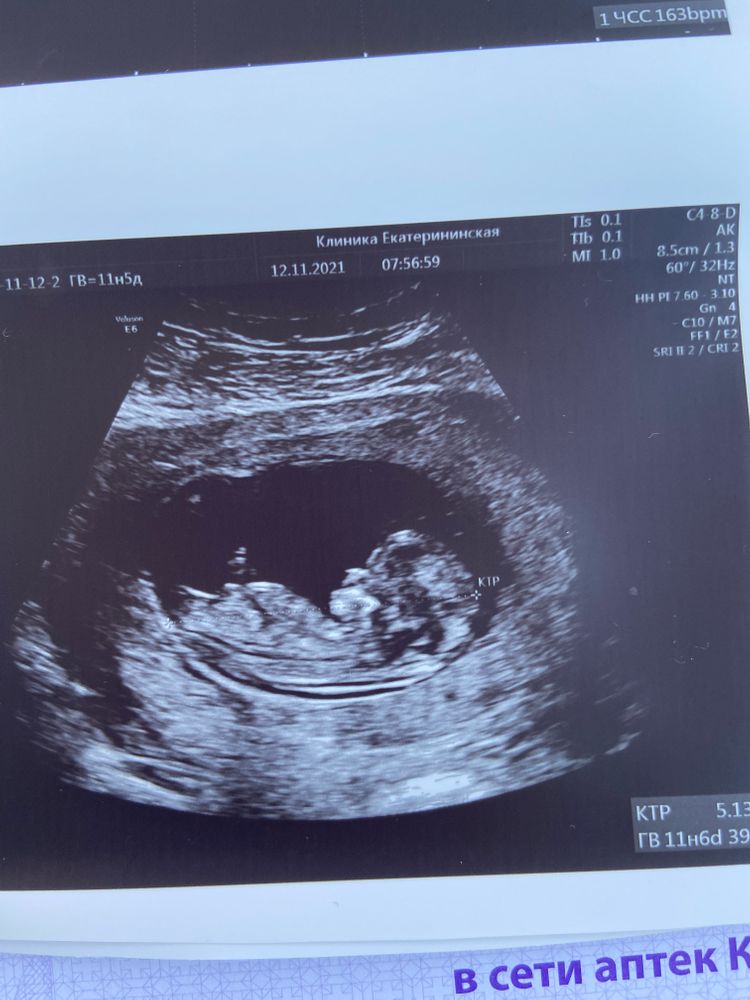

Первый скрининг!

Кровь еще жду, а вот УЗИ сделала!

По замерам все хорошо. Малышастик развивается четко по срокам! Фото отправила еще своему гинекологу - все хорошо!

11+5 )))

Пол не стали разглядывать - рано еще. За полом пойду перед новым годом)